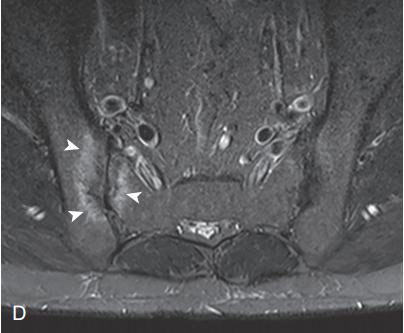

5,脊柱关节炎(spondyloarthritis, SpA),包括骶髂关节炎和脊柱炎;

图10,PsA病人的骶髂关节炎MRI表现